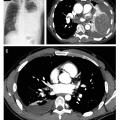

L’épanchement pleural liquidien peut être évoqué dans des circonstances particulières (tableaux 1 et 2) fondées sur la clinique, à l’occasion d’une douleur thoracique ou d’une dyspnée récente, d’un examen mettant en évidence une nette diminution, voire une abolition du murmure vésiculaire (le plus souvent en zone basale, mais parfois situé plus haut, en cas d’épanchement suspendu). Si l’échographie peut être utile, seule la radiographie thoracique permet le diagnostic : elle précise la localisation uni- ou bilatérale, basale ou enkystée, l’abondance, une compression éventuelle sur le médiastin ainsi que d’éventuelles lésions associées. Ces éléments sont fondamentaux pour éviter la réalisation d’examens inutiles et/ou potentiellement dangereux, notamment dans le cas d’un épanchement bilatéral, le plus souvent en lien avec une insuffisance cardiaque gauche. La radiographie thoracique ne permet pas toujours d’identifier une cause (aspect non spécifique), mais un épanchement suspendu ou multicloisonné (fig. 1) évoque en premier lieu une pleurésie infectieuse.

À la suite des examens de première intention, si le diagnostic reste méconnu, un scanner du thorax avec injection de produit de contraste est réalisé (fig. 2). Il permet de rechercher notamment une embolie pulmonaire, un rehaussement pleural nodulaire et une tumeur intra-thoracique.2